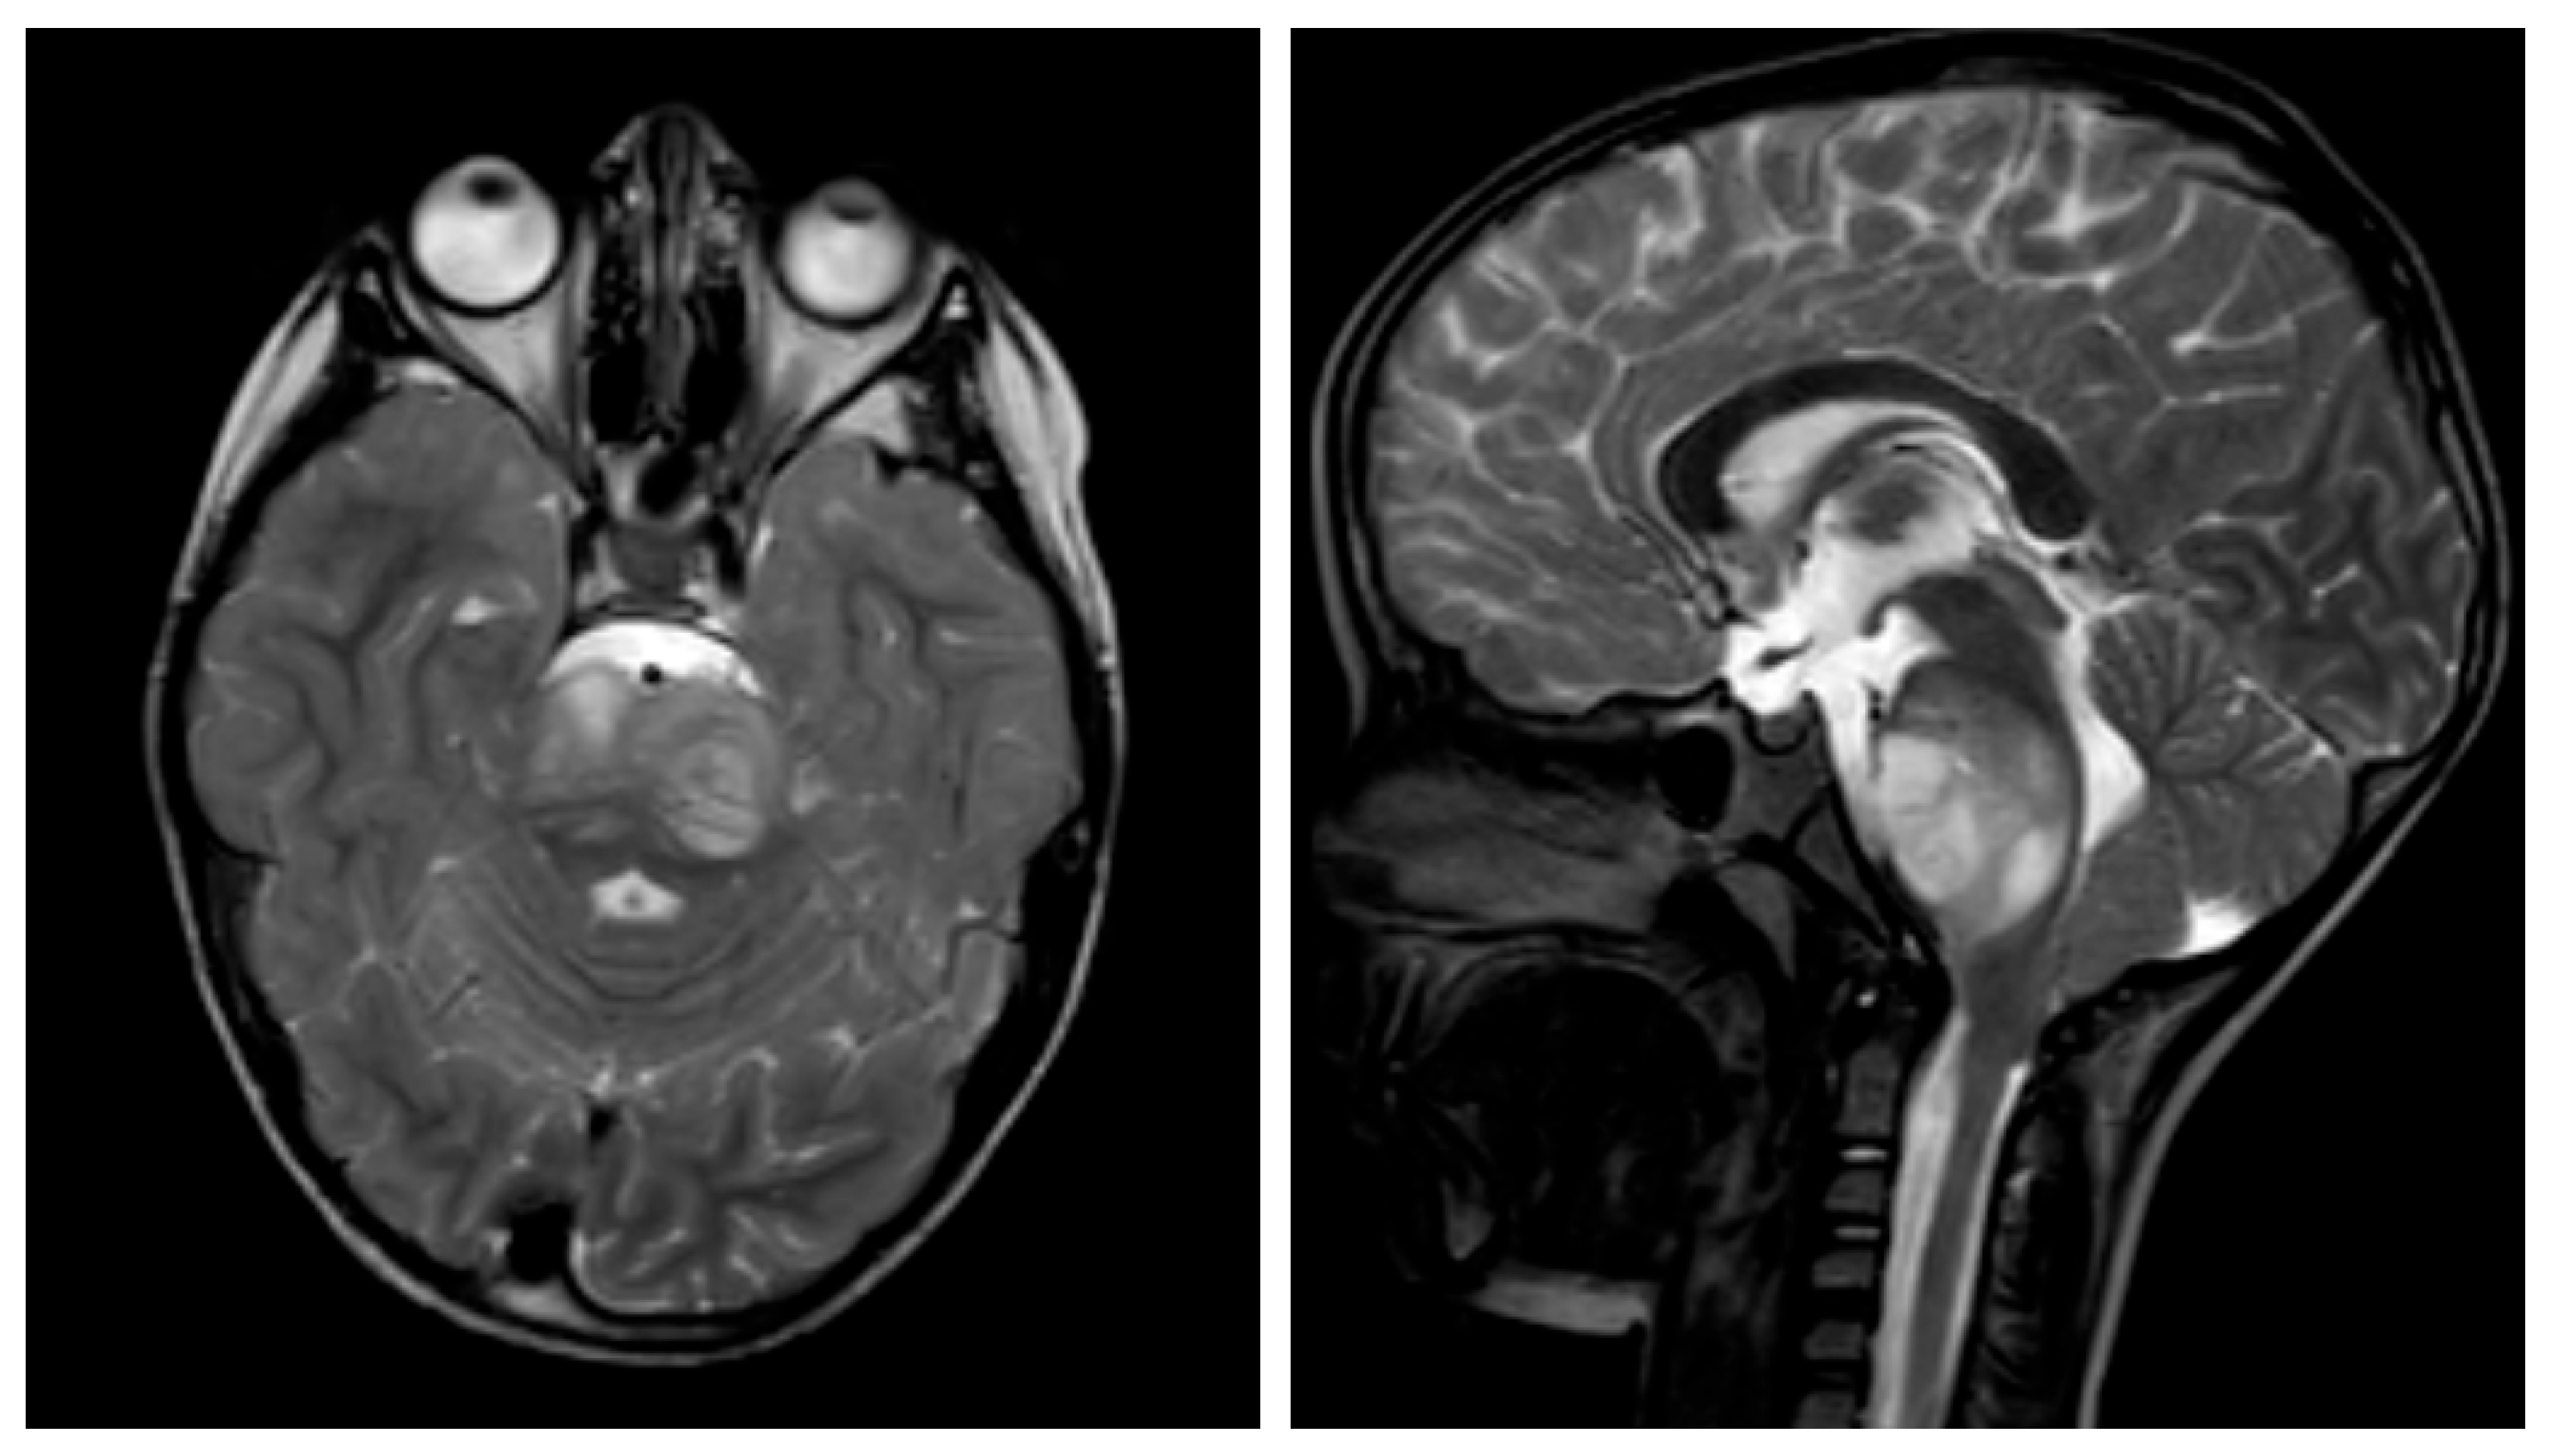

2.4. The Clinical Use of Miglustat in Two Patients with H3K27M-Mut DMG